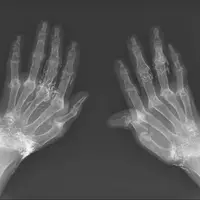

صادقپور ادامه داد: در شرایطی که مصرف روزانه میوه و سبزیجات کافی نباشد، استفاده از مکملهای ویتامین C میتواند مفید باشد، اما باید توجه داشت که مصرف بیش از دو گرم از این ویتامین در روز، ممکن است منجر به بروز عوارضی مانند اسهال، دلدرد، تهوع و افزایش احتمال تشکیل سنگ کلیوی اگزالاتی، بهویژه در افراد مستعد، شود.